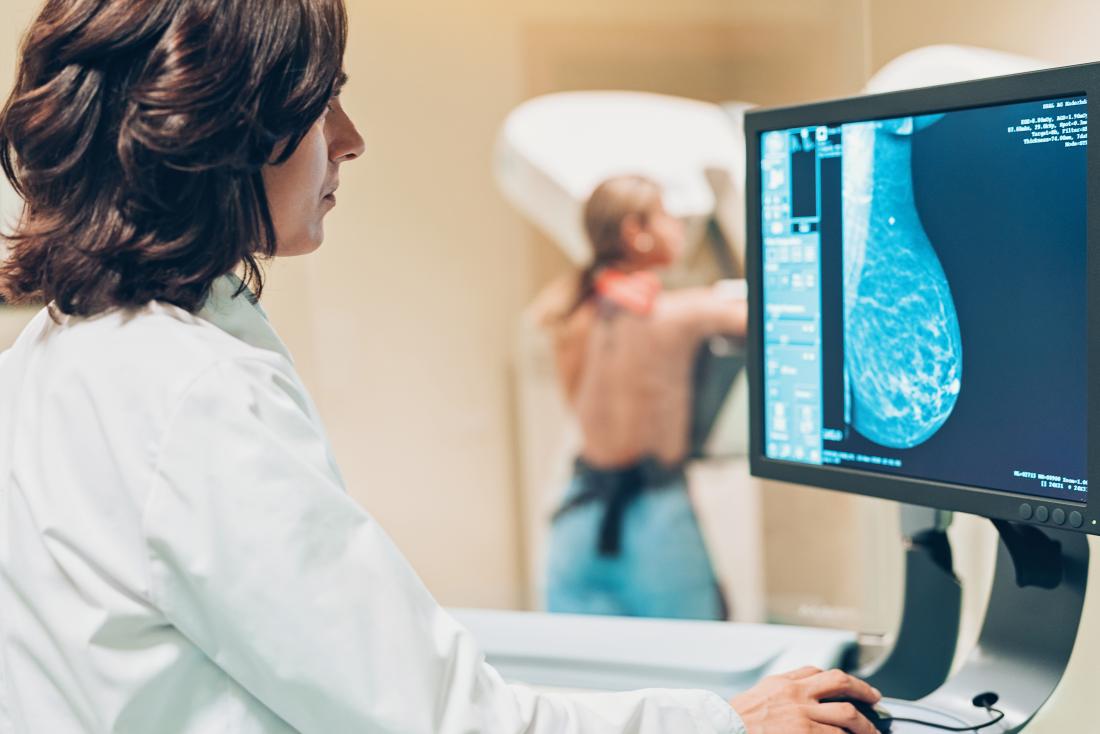

The experience of having a 3D mammogram feels the same as having a 2D one. You arrive at the breast center and change into a dressing gown. A radiology technician escorts you into a private mammography room with the 3D mammography machine. (It looks the same as a conventional 2D mammography machine.)

The technician helps you know how to position your body. The breast is supported by a tray while a flexible plastic plate is gently lowered down on top of the breast to press against the breast tissues.

A mammography tube then takes a series of low-radiation dose X-ray images at different angles, all within just a few seconds. The process is repeated for the other breast. The radiologist reads the images and sends a complete report to you and your doctor with the results.